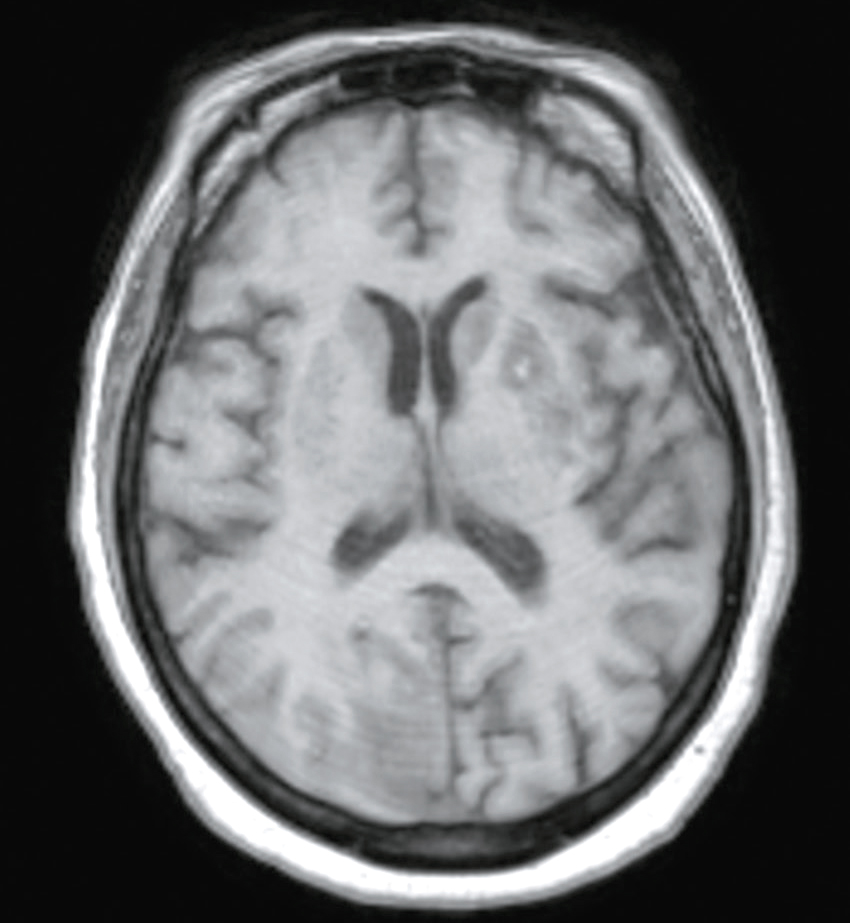

Une IRM cérébrale a été également réalisée (fig. 31.4). Quelle est la séquence présentée ?

L'image montre une IRM (Imagerie par Résonance Magnétique) du cerveau humain en coupe axiale, c'est-à-dire une vue transversale du cerveau prise horizontalement. Cette image est particulièrement intéressante car elle permet de visualiser les structures internes du cerveau avec une grande précision. On peut observer les globes oculaires en haut de l'image, qui apparaissent comme deux cercles blancs. Les différentes zones du cerveau sont visibles, avec des variations de teintes qui indiquent les différentes densités des tissus cérébraux. La région centrale lumineuse correspond au tronc cérébral, une structure cruciale pour de nombreuses fonctions vitales. Les zones plus sombres autour du tronc cérébral représentent les hémisphères cérébraux. Cette image est utilisée pour diagnostiquer et évaluer diverses conditions neurologiques, telles que les tumeurs, les accidents vasculaires cérébraux, les infections, et les anomalies structurelles. L'IRM est une technique non invasive qui utilise des champs magnétiques et des ondes radio pour produire des images détaillées des organes et des tissus internes.

- A T1

- B écho de gradient

- C T2

- D T2/FLAIR

- E diffusion